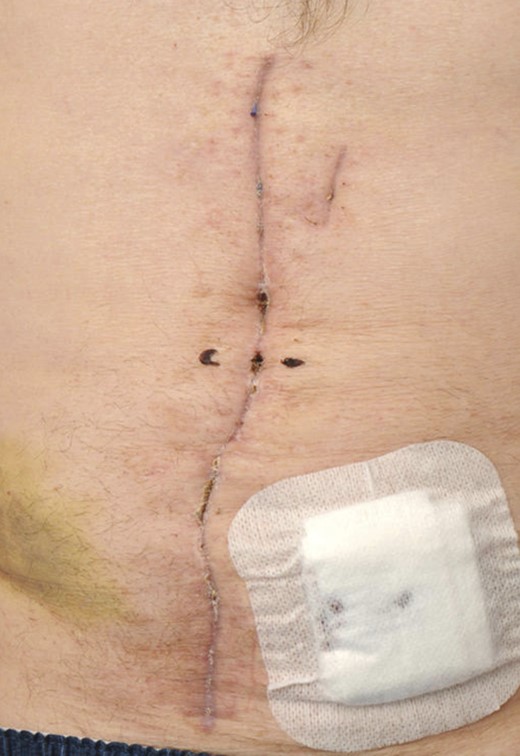

A posterior sheath release was then performed to provide medial movement of the sheath, so that it could be closed in the midline (see Fig. 3). A 25 × 25-cm biologic mesh (Strattice™ Reconstructive Tissue Matrix,–LifeCell Corp.) was rotated to a diamond shape and secured in the pre-peritoneal space, to the lateral fascia (see Fig. 4). The rectus muscle was closed, and the component separation allowed for the anterior sheath to be closed in the midline (see Fig. 5). Primary skin closure was undertaken, and the patient returned to the ward.

The rectus muscle has been closed, and a drain is placed prior to closing the skin.

On the 16th postoperative day, he suffered a witnessed ventricular fibrillation cardiac arrest. He was resuscitated and subsequently anticoagulated. The following day a computed tomography scan revealed a large abdominal wall haematoma anterior to the rectus sheath. He returned to theatre on the 17th postoperative day. The fascia was found to be intact, and the haematoma evacuated. Topical negative pressure was reapplied. On the 21st postoperative day, the skin was reclosed. He returned to the ward and was discharged on the 49th postoperative day, following implant of a cardiac defibrillator, with an intact wound (see Fig. 6).